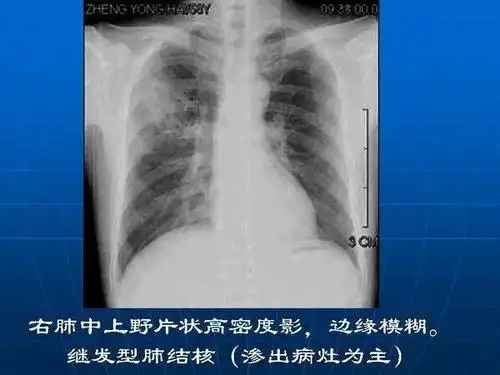

肺结核的影像诊断学习笔记丨影像天地

肺结核的影像诊断(x线)_第3页

各型肺结核的典型影像表现

浸润性肺结核